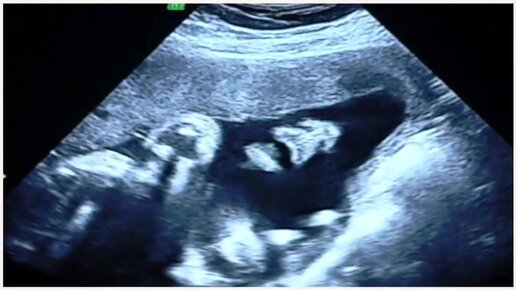

УЗИ на 31 неделе беременности